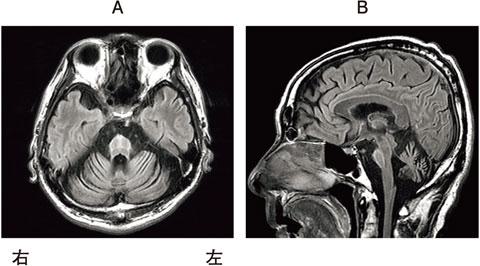

58歳の男性。生来健康であったが、突然のめまいと歩行困難で救急搬送された。脳梗塞の診断で理学療法が開始された。理学療法の初期評価では、めまい、眼振とともに、右側には小脳性の運動失調、Horner症候群および顔面の温痛覚障害がみられた。左側には上下肢の温痛覚障害がみられたが深部感覚は保たれていた。病巣はどれか。

1

2

3

4

5

56歳の男性。発症時に明らかな運動麻痺はないが、歩くとすぐによろけて物につかまっていないと立っていられなくなり、頭部CT検査で脳出血と診断された。頭部CT画像を示す。この患者の頭部CT画像として最も可能性が高いのはどれか。

①

②

③

④

⑤